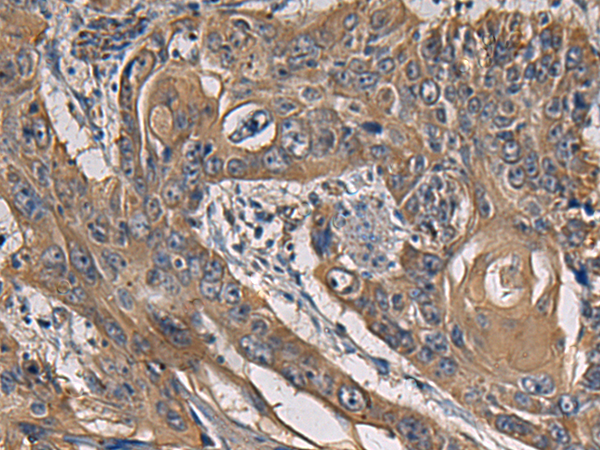

IHC positive control: |

Human esophagus cancer and Human colorectal cancer |

IHC Recommend dilution: |

50-200 |